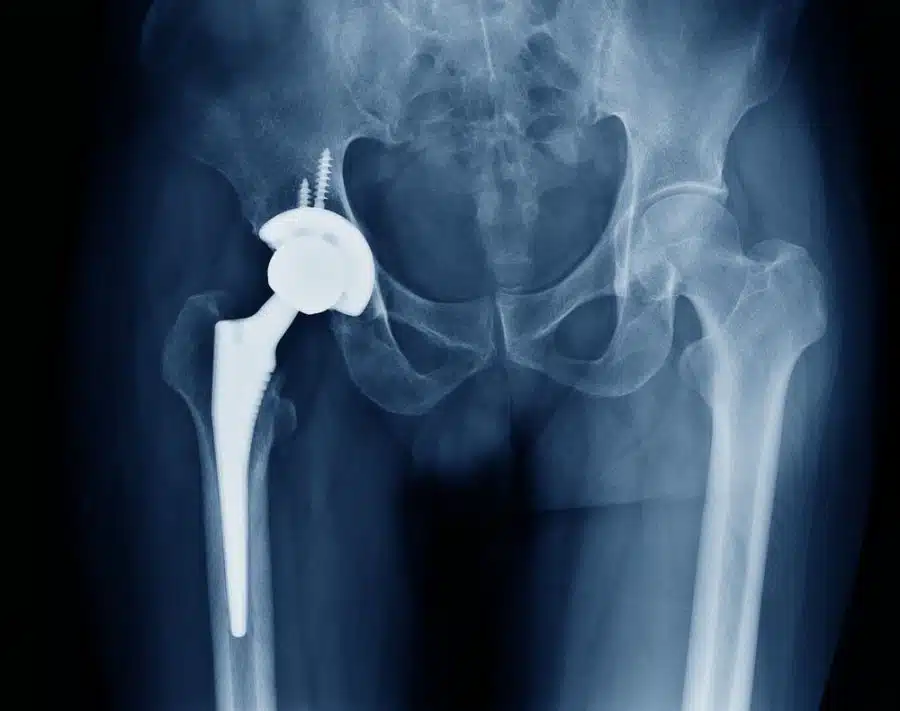

The general outline of a hip replacement surgery is to remove the damaged hip and replace it with prosthesis. The hip prosthesis is usually made up of a stem that connects the pelvic bone and thigh bone. It also consists of a cup that will be inserted into the hip joint’s socket. The cup and stem are made of metals (sometimes plastic or ceramic), while the head joint is made of ceramic. Moreover, hip prostheses have two different categories: cemented and non-cemented prosthesis. A non-cemented prosthesis attached to the bone with a special surface while the cemented one will be attached using surgical cement. In non-cement prosthesis, one side enters the femoral bone canal and other side fixes into pelvic bone. Sometimes surgeons prefer to combine these two types for replacing a hip.

In total hip replacement surgery, the surgeon removes the damaged bone marrow and replaces it with a metal sphere. The artificial hip joint matches two bones together. At the top is the acetabular cavity, which is a part of the pelvis. This cavity is approximately a hemisphere. Inside the cavity of the acetabulum is the femoral head.